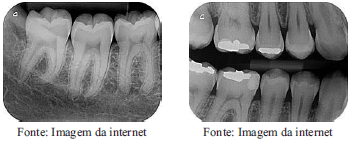

As imagens abaixo ilustram dois tipos de radiografias odontológicas. A denominação CORRETA dessas radiografia é, respectivamente:

periapical e interproximal.